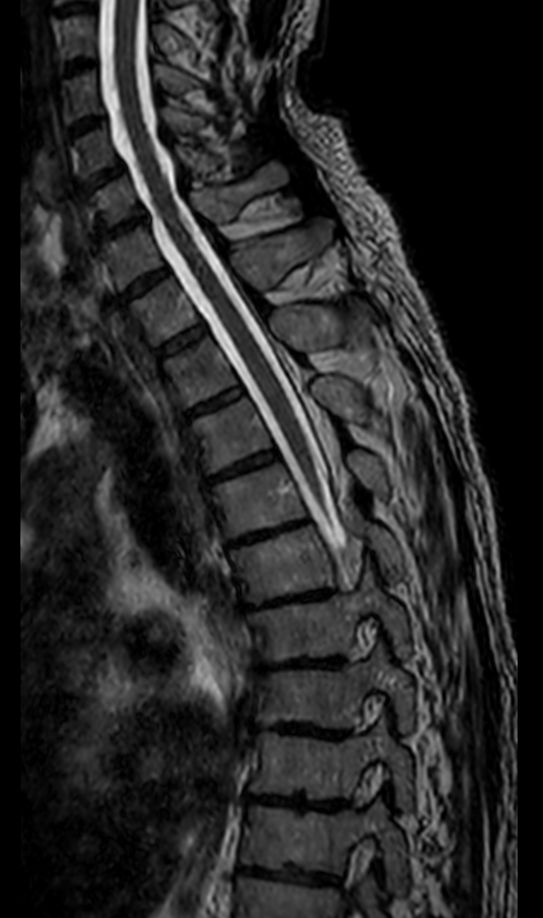

Sagittal T1w TSE (2 stations)Compressed SENSE

Sagittal T2w TSE (2 stations)Compressed SENSE

Sagittal STIR TSE (2 stations)Compressed SENSE

Sagittal 3D T2w TSE (SpineVIEW)Compressed SENSE